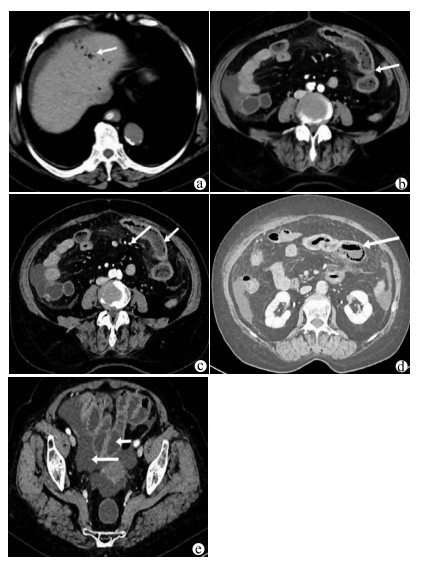

A case of acute hemorrhagic necrotizing enteritis with hepatic portal venous gas